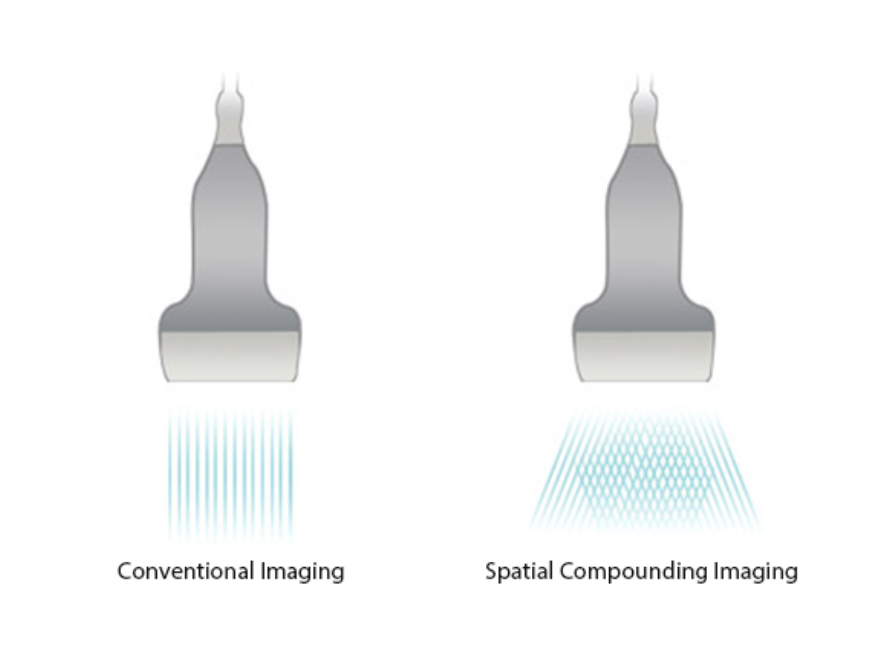

iBeam?

Permits use of multiple scanned angles to form a single image, resulting in enhanced contrast resolution and improved visualization.